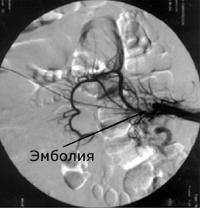

• Эмболический — вследствие смещения с током крови эмболов, первоначально возникающих проксимально, — из сердца (фибрилляция предсердий, постинфарктные изменения, заболевания клапанов) или из аневризмы атеросклеротической аорты. Эмболы обычно застревают в ВБА, но могут смещаться ниже, в среднюю толстокишечную артерию; следовательно, как правило, большинство проксимальных сегментов тонкой кишки не страдает. Эмболы также Склонны к фрагментации, при этом происходит дистальная реэмболия, вызывая сегментарный тип прерывистой ишемии.

При обзорной рентгенографии брюшной полости определяется пневматизация кишечника, наличие горизонтальных уровней жидкости в брюшной полости. Специфическим методом диагностики острой окклюзии мезентериальных сосудов является селективная мезентерикография, которая уже на ранней стадии заболевания может выявить отсутствие кровотока в стволе и ветвях брыжеечной артерии. При наличии технической возможности выполняется магнитно-резонансная ангиография мезентериальных сосудов.